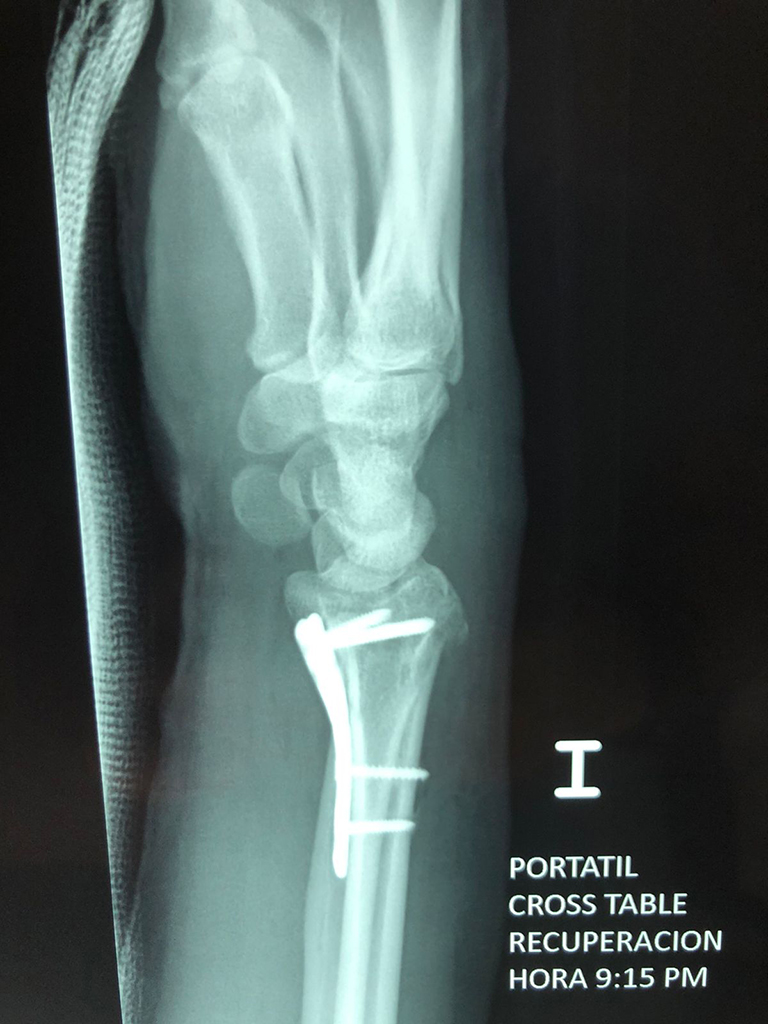

Cirugías de Muñecas

Los procedimientos más comunes en cirugía de la mano son aquellos destinados a reparar traumatismos, incluyendo lesiones de tendones, nervios, vasos sanguíneos, y articulaciones; huesos fracturados; y quemaduras, cortes, y otros daños de la piel.